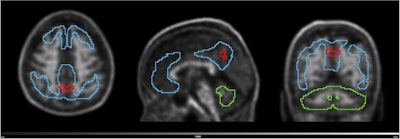

PET scans identify people at early risk for cognitive decline. Image from Guilherme Kolinger, MD, of Life Molecular Imaging in Germany, et al.

The study was conducted by scientists at Lantheus subsidiary Life Molecular Imaging, with the image demonstrating how quantitative analysis can reveal additional insights beyond standard visual assessment in amyloid PET.

“To identify the region highlighted in red, an amyloid-negative population (at baseline) with subjective cognitive decline was assessed with a voxel-based analysis using standardized uptake value ratios (SUVRs). Then, the baseline SUVR images of amyloid accumulators versus nonaccumulators were compared. Amyloid accumulation status was defined using the Centiloid method and with a five-year follow-up,” lead author Guilherme Kolinger, MD, explained to AuntMinnie.

The results showed that accumulators exhibited higher baseline SUVR in the red-marked region, which corresponds to part of the precuneus, a brain area known to play a role in early Alzheimer’s disease. This region overlaps with the Centiloid target region (shown in blue), underscoring the potential of this approach to enhance preclinical Alzheimer’s disease assessment, Kolinger added.